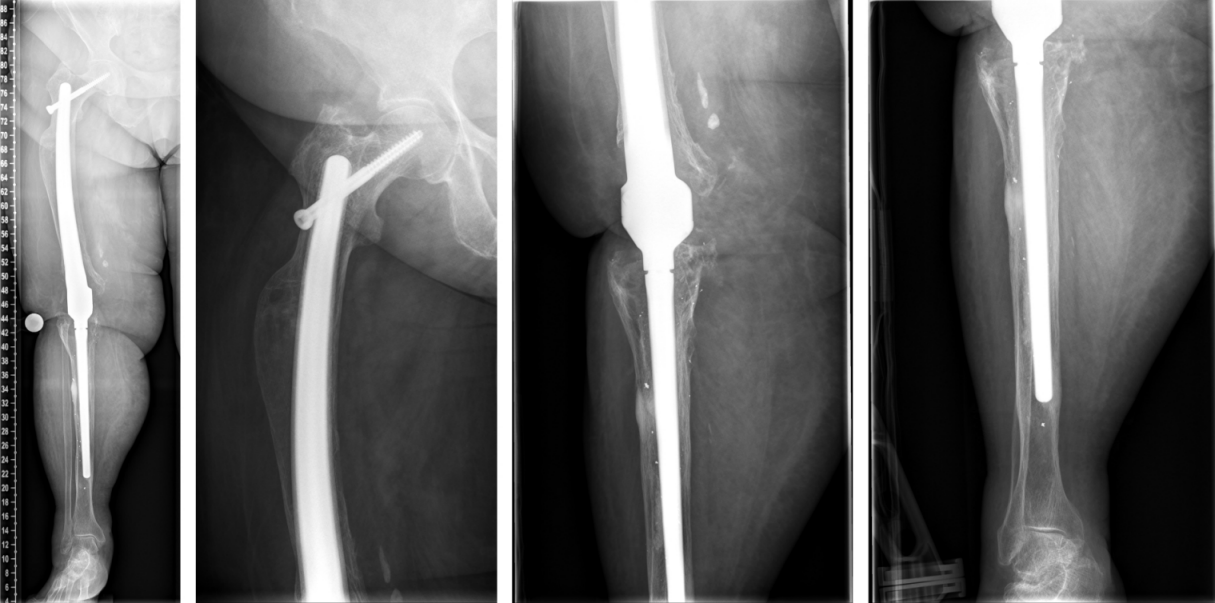

The duration of the surgical intervention was four hours and eight minutes. The patient was then mobilized with full weight bearing supervised by physiotherapists at ward level, which she tolerated well. The pain was significantly relieved during the hospital stay. The postoperative radiographs showed correct implant position and a satisfactory surgical result (Figure 9 [Fig. 9]). Microbiological and histological samples obtained intraoperatively showed no evidence of infection. Yet, the patient presented postoperatively with complete loss of active dorsiflexion of the ipsilateral foot. Neurological consultation and investigation confirmed the diagnosis of peroneal lesion. The patient was supplied by orthopedic shoes and orthesis. Further, electrotherapy was carried out.

Figure 9: The postoperative radiographs showed correct implant position and a satisfactory surgical result.

On one-year follow-up, the patient did not complain of any pain. The radiological findings one year after surgery showed no sign of loosening or any other pathological findings (Figure 10 [Fig. 10]). The neurological lesion has completely recovered. The Harris Hip Score HHS improved from 24 (prior to implantation of the arthrodesis) to 75 on one-year follow-up, the Western Ontario and McMaster Universities Osteoarthritis Index WOMAC improved from 86 to 20. The range of motion of the right hip joint one year after surgery was: extension/flexion 0/0/100°, abduction/adduction 30/0/20°, external rotation/internal rotation 30/0/20°.

Figure 10: The radiological findings one year after surgery show no sign of loosening or any other pathological findings.